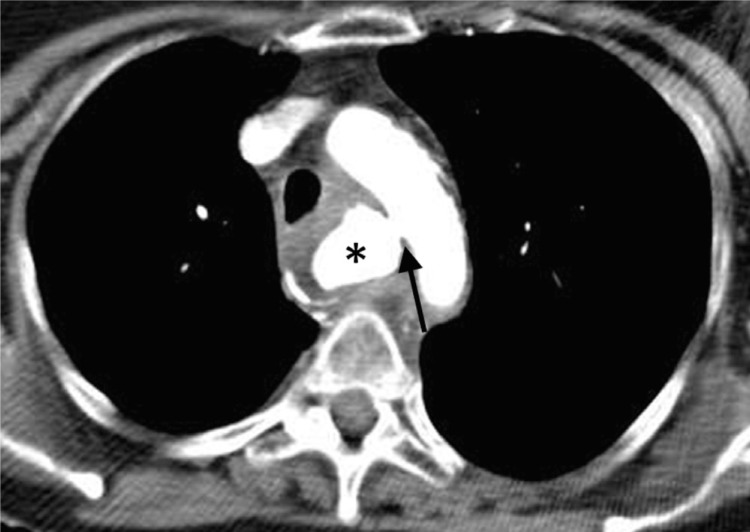

Aorto‑esophageal fistulas (AEF) are rare, often fatal connections between the thoracic aorta and esophagus, arising from aortic disease, esophageal conditions, or iatrogenic causes. Case: A 76‑year‑old woman, treated for esophageal nutcracker syndrome with endoscopic injection of botox, developed chest pain and esophageal hemorrhage. Computed tomography (CT) confirmed an AEF from an aortic pseudoaneurysm. She succumbed to circulatory collapse before treatment. Discussion: Endoscopic botox injections are a rare cause of AEF. The diagnosis relies on imaging and endoscopy, with surgery often required. Teaching point: Aorto‑esophageal fistulas are rare, life‑threatening complications, particularly after iatrogenic procedures. Early diagnosis is crucial, but prognosis remains poor.